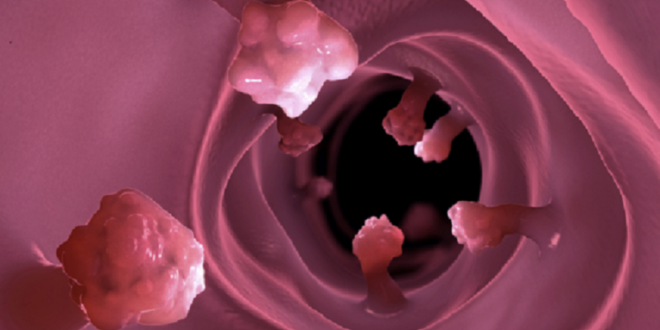

وتشير الأخصائية، إلى أن سرطان القولون يتطور من زائدة لحمية صغيرة (سليلة) في الغشاء المخاطي، تتضخم مع مرور الوقت إلى ورم حميد أو ورم خبيث. لذلك إزالة هذه الزائدة تمنع الإصابة بسرطان القولون بنسبة تصل إلى 95 بالمئة.